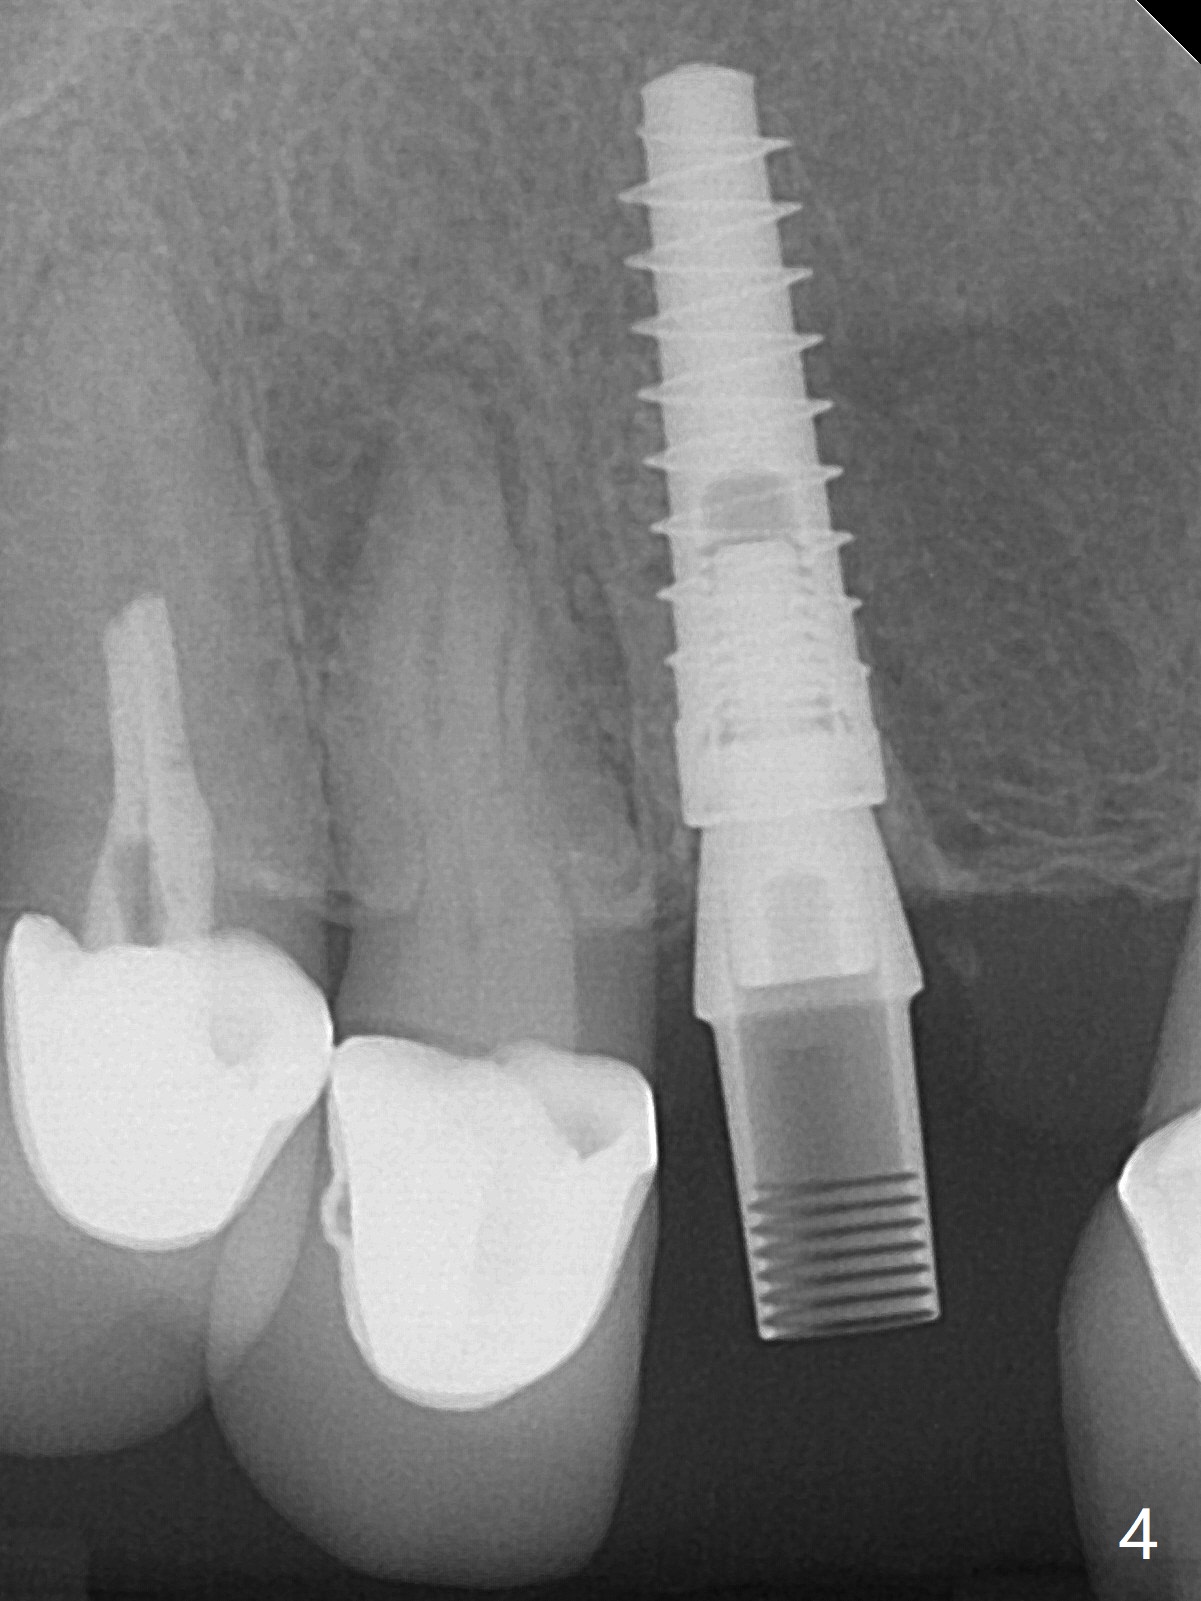

To reduce the large black triangle between the lateral incisor/canine and central incisor (Fig.1 *), osteotomy is not established mesial enough initially (Fig.2). Since the bone density is not high, trajectory change is not attempted. The ridge is wider within the socket. A relatively large 2-piece implant (3.5x13 mm) is placed (Fig.3), but a 4x5.7(2) mm abutment is incompletely seated (<). Use of 4.6 and 5.6 mm bone profile drills does not appear to solve the problem. The implant is backed up to the supra-gingival level so that it seems easier physically to insert the same abutment into the implant. Then both of them are torqued into the place together (Fig.4). An immediate provisional is fabricated to close the gingival embrasure as much as possible (Fig.5). Consider reducing the provisional margin (arrow) as early as possible postop. In fact the patient agrees to have a new crown made for #8 to further close the embrasure. The bone graft remains in place 4 months postop (Fig.6). The gingiva is healthy around the provisional 4.5 months postop (Fig.7). The gingival embrasure with a permanent restoration is smaller than that before treatment (Fig.8). Return to No Deviation Prevent Screw Loosening Prosthetic Planning Kit Webinars Xin Wei, DDS, PhD, MS 1st edition 02/11/2020, last revision 07/09/2020